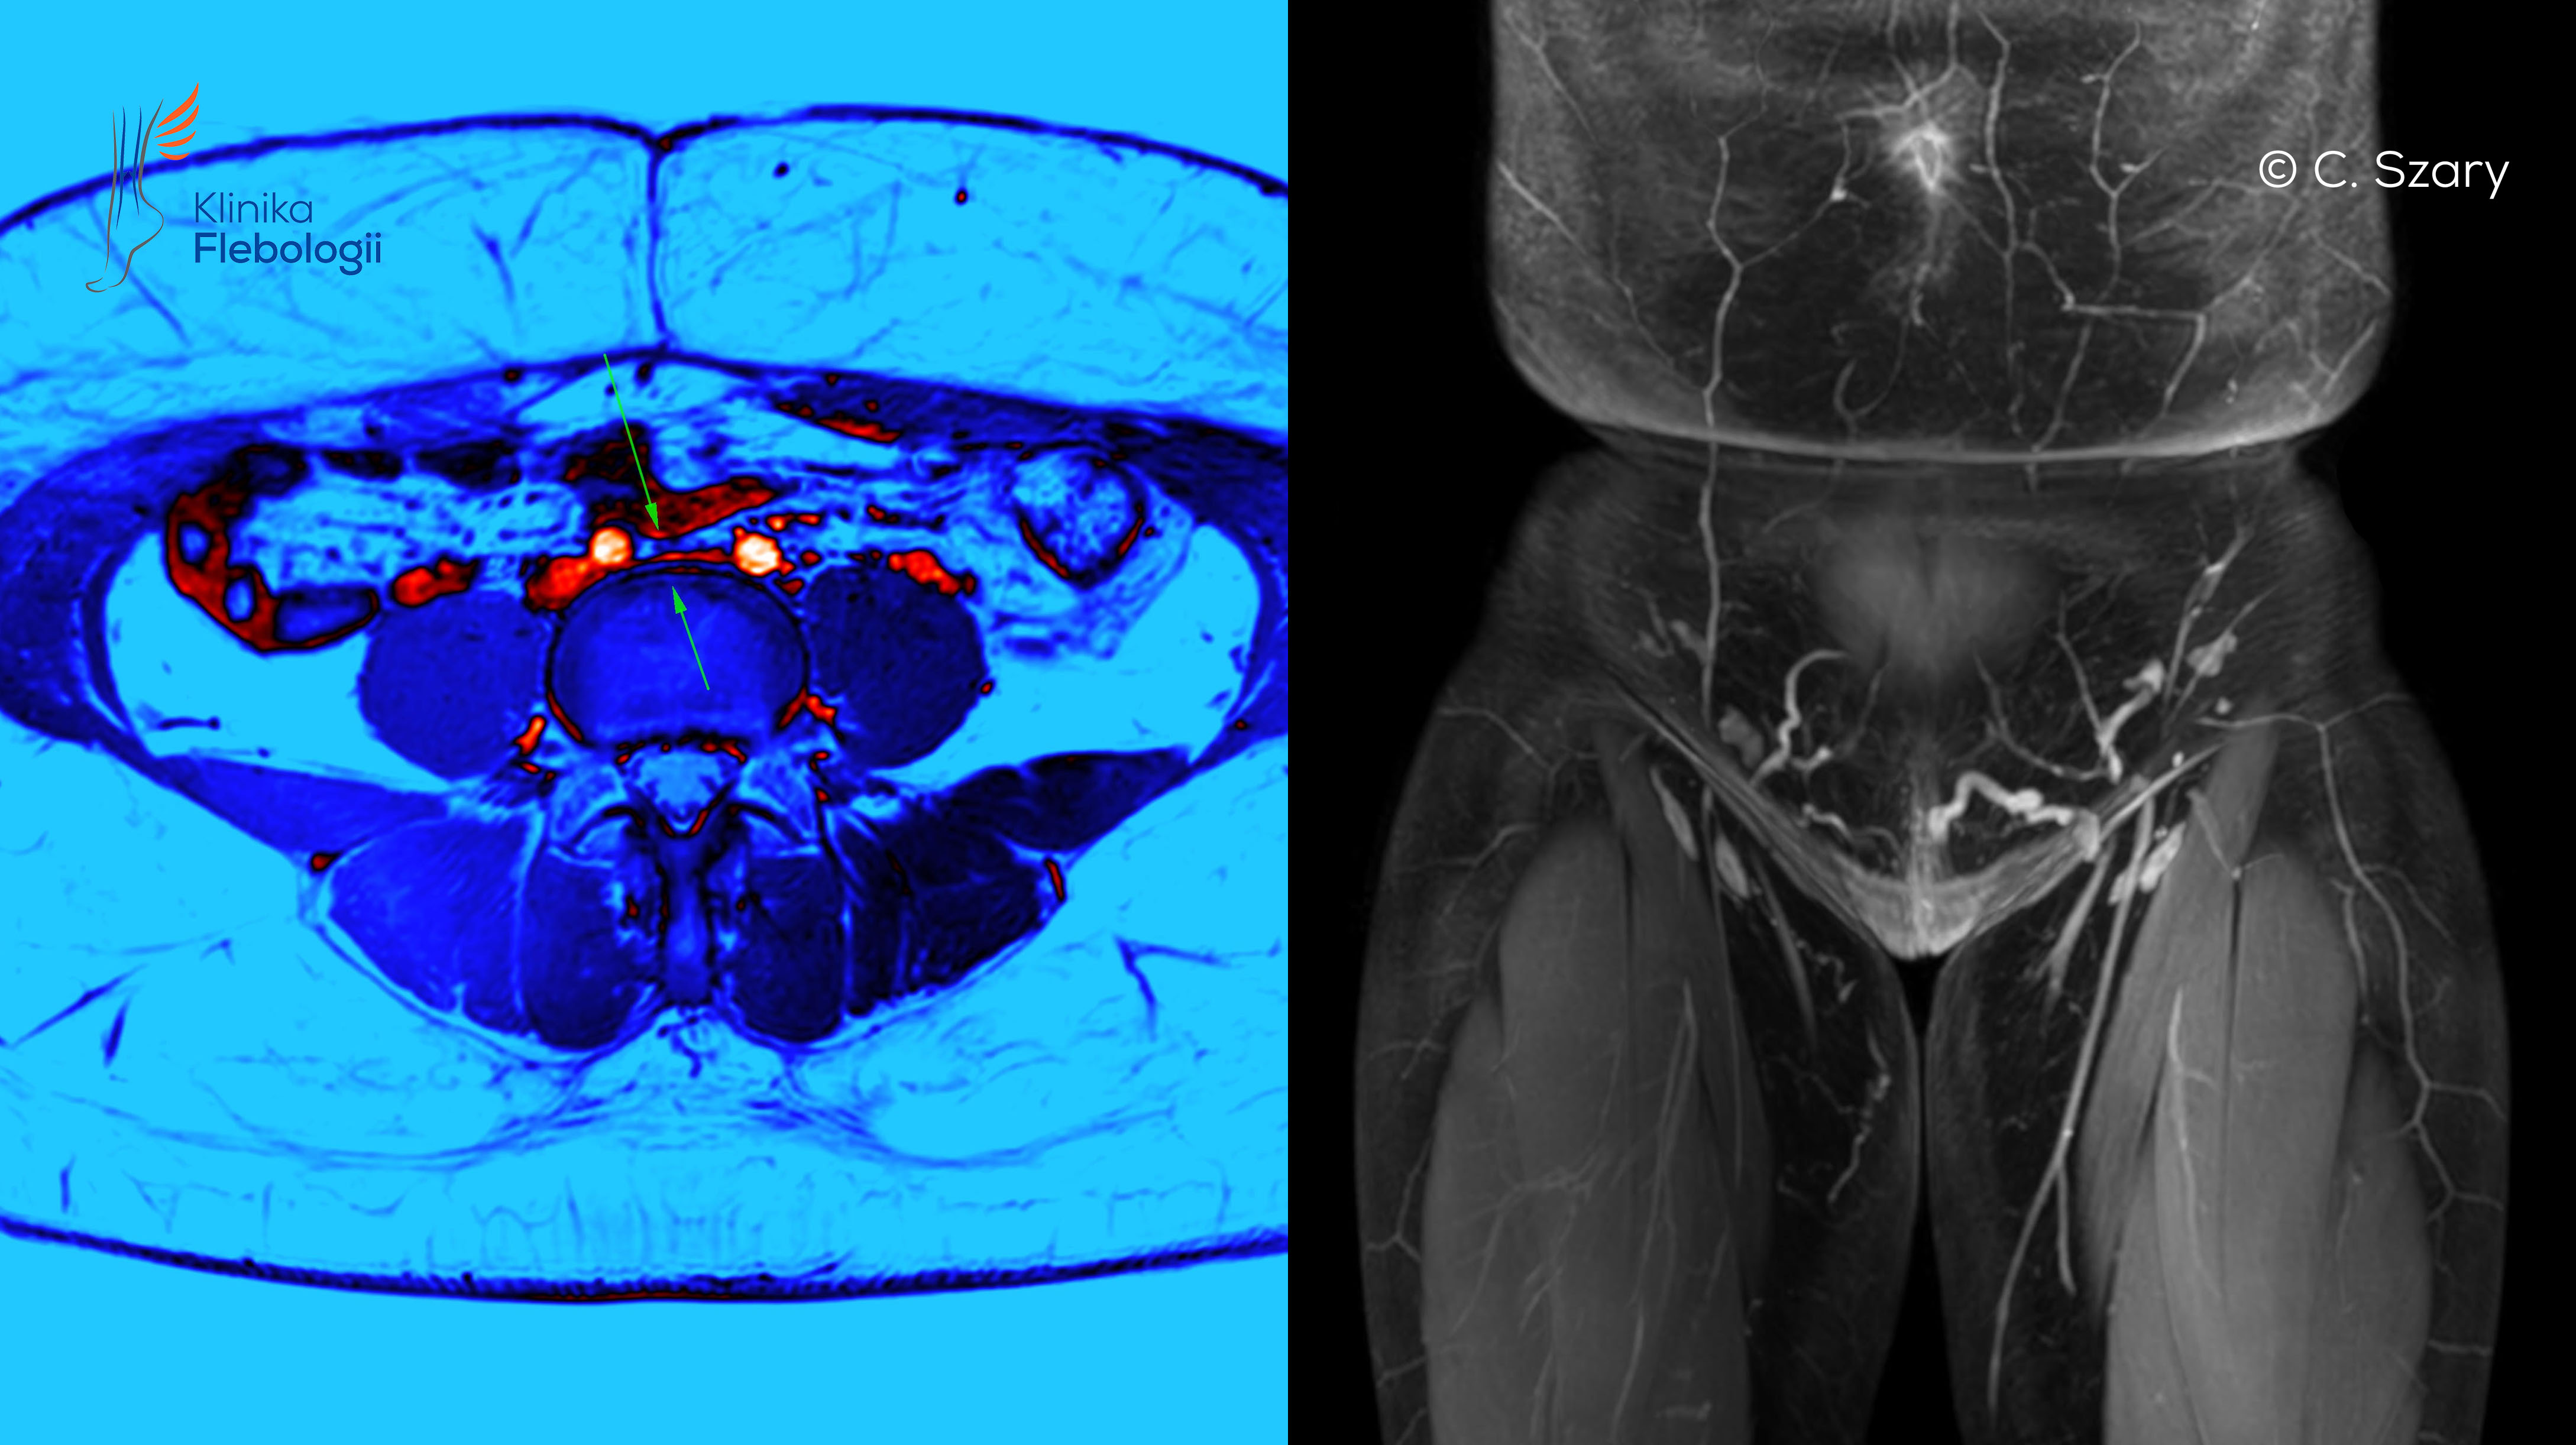

Zespół May-Thurnera związany jest ze zjawiskiem zaburzonego odpływu krwi żylnej z obszaru spływu układu żył biodrowych po lewej stronie ciała. Do ucisku dochodzi typowo na poziomie skrzyżowania tętnicy biodrowej wspólnej prawej z żyłą biodrową wspólną lewą. Ujawnianie się tego typu nieprawidłowości anatomicznych występuje częściej u kobiet. W wielu przypadkach pewne objawy skrzyżowania naczyń widoczne są już przed porodem, a w sposób najbardziej dobitny po urodzeniu pierwszego dziecka

Zjawisko May-Thurnera po raz pierwszy dokładnie opisane zostało w roku 1965. Współcześnie definiowane jest ono jako utrudnienie odpływu krwi żylnej z poziomu kończyny dolnej lewej powstałe wskutek obecności zmian o typie przegrody (przegród) w świetle lewej żyły biodrowej wspólnej lewej lub z powodu jej ucisku, wywołanego przez przebiegającą w bezpośredniej bliskości tętnicę biodrową wspólną prawą.

Ucisk lewej żyły biodrowej wspólnej na poziomie jej skrzyżowania z prawą tętnicą biodrową wspólną i niekorzystne konsekwencje z tego wynikającego, to jedno z ważniejszych zjawisk anatomicznych w układzie żylnym, doprowadzające do wczesnej niewydolności żylnej miednicy, niewydolności żylnej kończyn dolnych (częściej lewej), a także groźnej dla życia zakrzepicy proksymalnej w lewej kończynie dolnej.

Określenie zespół May-Thurnera używane jest wyłącznie w sytuacjach, gdy niewłaściwa konfiguracja naczyń powoduje występowanie objawów typowych dla zaburzonego odpływu krwi żylnej.

Zjawisko May-Thurnera ujawnia się najczęściej u kobiet będących w ciąży. Wynika to bezpośrednio ze zwiększającej się ciasnoty w czasie wzrastania płodu i dodatkowych niesprzyjających warunków w odpływie krwi żylnej z miednicy.